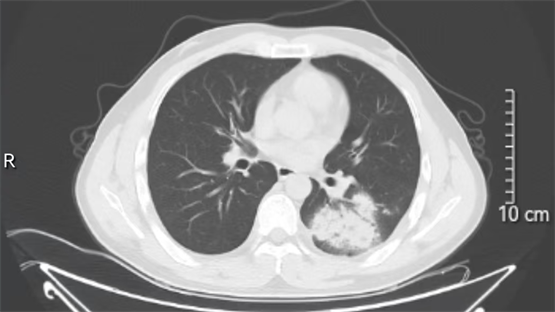

2. 胸部影像学检查

· 胸部CT:比胸片更清晰,能发现早期病灶(如结核结节、空洞、渗出影),判断病变部位和严重程度;

· 胸片:可初步筛查肺结核,但对微小病灶或隐蔽部位(如纵隔、胸膜)的诊断价值有限。